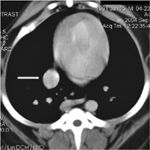

One might be tempted to say that a tumor that rarely spreads to the lungs does not require thoracic radiography, but I cannot think of any instance in a cancer patient's work-up in which looking at the thorax is unnecessary.